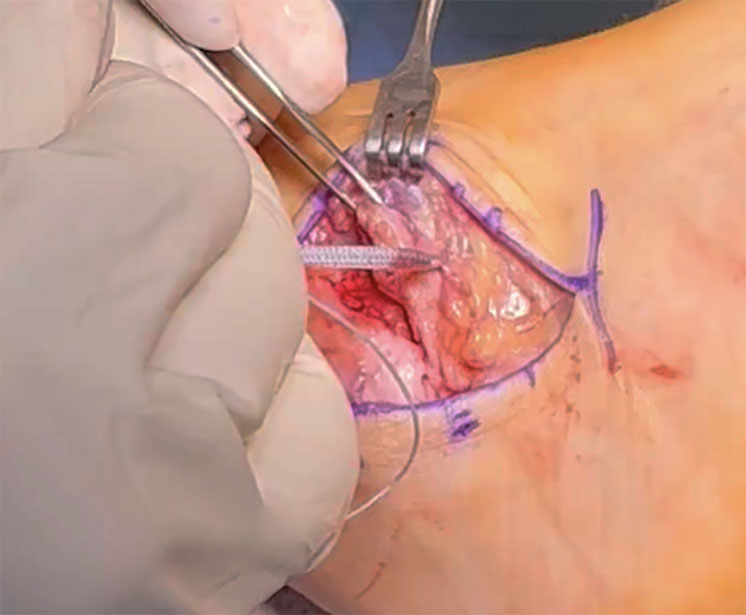

OVT video shows hypothenar fat pad flap is a reliable way to obtain local coverage of the median

Carpal tunnel syndrome is one of the most prevalent focal mononeuropathies, constituting 90% of neuropathy cases.